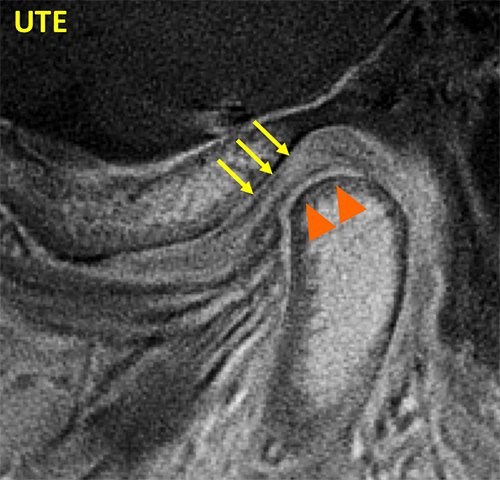

TMJ UTE

UTE sequence of the TMJ shows bright signal in the disc (arrows) and in the fibrocartilage covering the mandibular condyle (arrowhead).